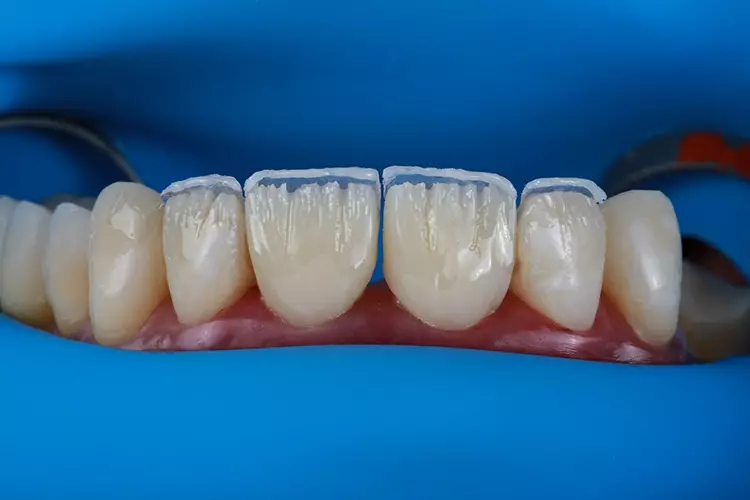

Das für das Mock-up verwendete Material bestand aus selbsthärtendem Mikro-Hybrid-Komposit für provisorische Kronen und Brücken (Structur 2, VOCO). Das thermoviskose VisCalor bulk (VOCO) wurde additiv in einen weiteren Silikonschlüssel injiziert, um die okklusalen Aspekte zahlreicher OK-Zähne sowie der rechten unteren Prämolaren und Molaren des Unterkiefers direkt im Mund zu rekonstruieren. Die Eckzahnführung wurde hingegen mit Admira Fusion (VOCO) wiederhergestellt.

Die Kronen für 11 und 21 wurden mit einer 5-Achs-Fräs- und Schleifmaschine (inLab MC X5; Dentsply Sirona) aus einer nanokeramischen Komposit CAD/CAM-Ronde (Grandio disc, A1, VOCO) gefräst und mit Bifix Hybrid Abutment (VOCO) auf einem Abutment aus Metall (Grand Morse, Neodent Titanium Base Neodent, Straumann) im Labor zementiert. Die Kronen wurden in ihrer endgültigen Position eingegliedert (Abb. 18). Jede Krone wurde mit direkten Komposit-Veneers modifiziert.

Letztendlich hängt der Behandlungserfolg weniger von der Erfahrung der Behandelnden als vielmehr von der Beachtung und Einhaltung der Planungs- und Ausführungsprotokolle bei der Anwendung der Technik ab. Eine direkte Schichtung von Komposit-Veneers ist preisgünstiger als herkömmliche keramische Veneers und kann in nur einer Behandlungssitzung durchgeführt werden.